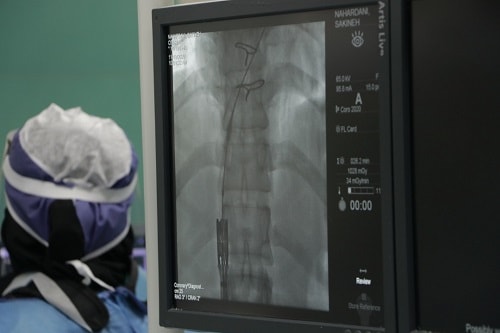

نخستین عمل کارگزاری دریچه قلب بدون نیاز به جراحی بر روی دو بیمار با موفقیت در مرکز آموزشی پژوهشی درمانی امام رضا(ع) از مراکز زیر پوشش دانشگاه علوم پزشکی مشهد انجام شد.

استاد گروه قلب و عروق دانشگاه علوم پزشکی مشهد در گفتگو با وب دا اظهار کرد: این عمل بر روی یک خانم 38 ساله ویک آقای 36 ساله که پیش از این تحت عمل جراحی باز تعویض دریچه قلب قرار گرفته بودند و پس از گذشت چند سال دچار مشکل شده بودند و با توجه به ریسک بالا امکان عمل جراحی باز مجدد وجود نداشت ، به روش آنژیوگرافی انجام شد.

دکتر محمود شبستری ضمن قدردانی از همراهی و همکاری دکتر حاج زینعلی  از اساتید قلب وعروق دانشگاه تهران  افزود : در این روش همان دریچه قلبی بافتی از طریق پوست مانند آنژیوگرافی ساده وارد قلب می شود و بر روی دریچه قبلی که دچار اشکال شده بوده کارگزاری می شود.